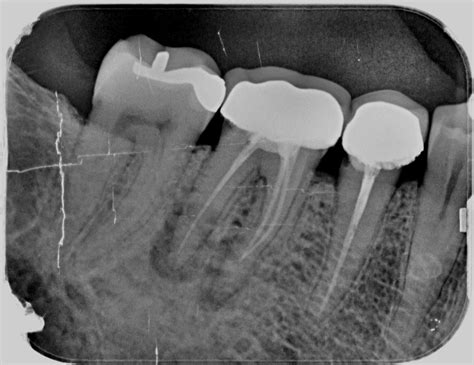

- No hacer radiografías durante la endodoncia: Tradicionalmente hay que realizar cinco radiografías en el transcurso de una endodoncia. Como norma siempre ha habido que realizar cinco radiografías durante el proceso de las endodoncias. Durante este proceso es conveniente realizar cinco radiografías para entender la situación de forma holística. Que no se hayan hecho radiografías durante el proceso de la endodoncia y tampoco se haya planificado la intervención.

- Calcular mal la longitud de trabajo: Debemos medir meticulosamente la longitud de cada conducto. Para ello utilizamos un dispositivo que se denomina localizador de ápices. Además, a pesar de lo que nos indique el localizador, es importante hacer una radiografía de comprobación para asegurarnos de que el localizador no se equivoca. Se suele utilizar un dispositivo denominado localizador de ápices para tener un control al detalle. Al calcular la longitud de cada producto afectado se debe medir con mucho cuidado y exactitud. Para ello, se utiliza un dispositivo llamado localizador de ápices. Por último, otro de los errores más comunes que afectan al resultado final es no calcular adecuadamente la longitud de los conductos.

- No obturar correctamente los conductos radiculares: Una vez eliminada toda la pulpa de los conductos, pasaremos a obturarlos con un producto que denominamos gutapercha. Es muy importante que la gutapercha esté bien condensada y rellene los conductos perfectamente de manera tridimensional. Una vez que se haya eliminado la pulpa por completo de los conductos afectados. Una vez eliminada toda la pulpa de los conductos, se procede a obturar con una gutapercha.